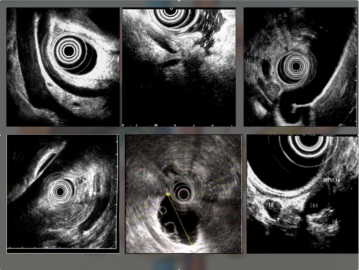

Второй выступающий – заведующий эндоскопическим отделением, к.м.н. Станислав Юрьевич Орлов поделился с собравшимися подробностями применения такого сравнительно нового метода эндоскопических исследований, как ультрасонография пищеварительного тракта, с помощью которой нашим врачам удается диагностировать

десятки различных заболеваний, включая язвенные кровотечения, кистозные образования поджелудочной железы, острый и хронический панкреатит и даже

карциноиды. С апреля 2017 г. в больнице было проведено более 80 ультрасонографических исследований.